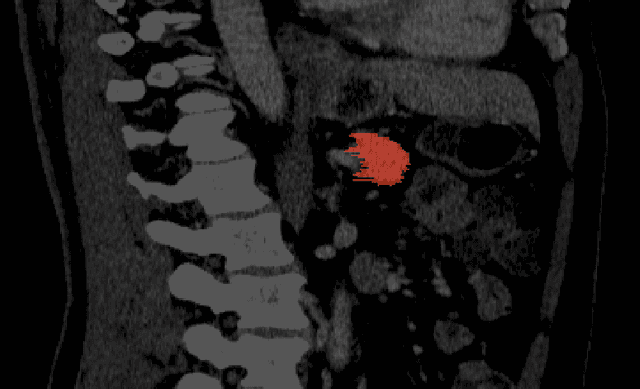

Abstract:There is a large body of literature linking anatomic and geometric characteristics of kidney tumors to perioperative and oncologic outcomes. Semantic segmentation of these tumors and their host kidneys is a promising tool for quantitatively characterizing these lesions, but its adoption is limited due to the manual effort required to produce high-quality 3D segmentations of these structures. Recently, methods based on deep learning have shown excellent results in automatic 3D segmentation, but they require large datasets for training, and there remains little consensus on which methods perform best. The 2019 Kidney and Kidney Tumor Segmentation challenge (KiTS19) was a competition held in conjunction with the 2019 International Conference on Medical Image Computing and Computer Assisted Intervention (MICCAI) which sought to address these issues and stimulate progress on this automatic segmentation problem. A training set of 210 cross sectional CT images with kidney tumors was publicly released with corresponding semantic segmentation masks. 106 teams from five continents used this data to develop automated systems to predict the true segmentation masks on a test set of 90 CT images for which the corresponding ground truth segmentations were kept private. These predictions were scored and ranked according to their average So rensen-Dice coefficient between the kidney and tumor across all 90 cases. The winning team achieved a Dice of 0.974 for kidney and 0.851 for tumor, approaching the inter-annotator performance on kidney (0.983) but falling short on tumor (0.923). This challenge has now entered an "open leaderboard" phase where it serves as a challenging benchmark in 3D semantic segmentation.

Abstract:The morphometry of a kidney tumor revealed by contrast-enhanced Computed Tomography (CT) imaging is an important factor in clinical decision making surrounding the lesion's diagnosis and treatment. Quantitative study of the relationship between kidney tumor morphology and clinical outcomes is difficult due to data scarcity and the laborious nature of manually quantifying imaging predictors. Automatic semantic segmentation of kidneys and kidney tumors is a promising tool towards automatically quantifying a wide array of morphometric features, but no sizeable annotated dataset is currently available to train models for this task. We present the KiTS19 challenge dataset: A collection of multi-phase CT imaging, segmentation masks, and comprehensive clinical outcomes for 300 patients who underwent nephrectomy for kidney tumors at our center between 2010 and 2018. 210 (70%) of these patients were selected at random as the training set for the 2019 MICCAI KiTS Kidney Tumor Segmentation Challenge and have been released publicly. With the presence of clinical context and surgical outcomes, this data can serve not only for benchmarking semantic segmentation models, but also for developing and studying biomarkers which make use of the imaging and semantic segmentation masks.